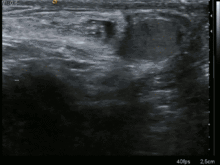

فتق مَغبـِنی (به انگلیسی: Inguinal hernia) به فتق در ناحیه کانال اینگوینال (کشاله ران) اطلاق میشود.

به پیش رفتگی درونی و خروج یکی از احشا (اندرونه) یا فاسیای اندام یا بخشی از آن در دیوارهای که بهطور طبیعی آن را دربر میگیرد از طریق یک معبر یا کانال یا روزنه آناتومیک فتق گفته میشود.